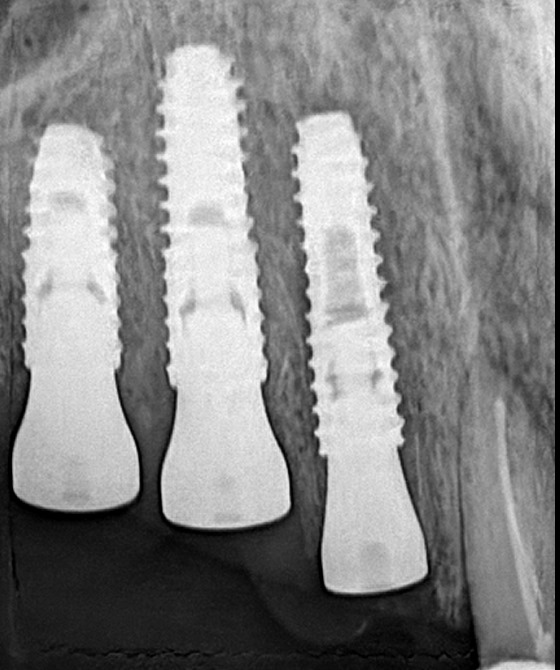

Implant Gallery